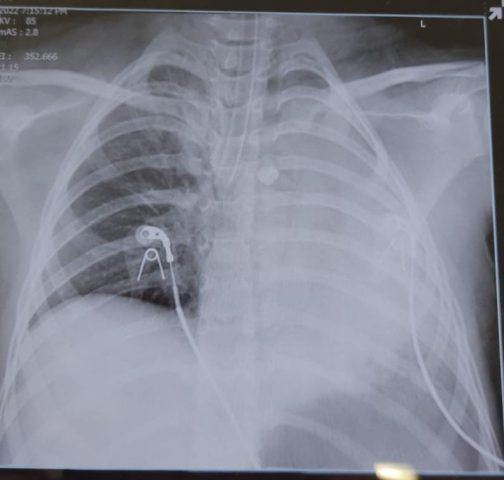

צפו: שן החלב שנשאפה לריאות

בצלאל התלוננה על כאב בזמן נשימה עמוקה, לכן החליטו ההורים לקחת אותה למרפאה מקומית שם הוחלט לבצע צילום דימות ובדיקה טכנית על מנת לוודא שהשן שנבלעה לא נמצאת בוושט, לאחר הבדיקה ובעקבות תלונות הילדה הומלץ להורים להגיע למיון ילדים.

מה שאירע ככל הנראה: "השן שנשאפה מוקדם יותר והתמקמה בריאה השמאלית של בצלאל, זזה ועלתה למעלה, כשמיקומה החדש חוסם את דרכי הנשימה של הילדה. בתוך זמן קצר חלה החמרה במצבה והיא התמוטטה כשהיא סובלת מקוצר נשימה" כך הסבירו בבית החולים.

"בשלב מסוים נשקפה סכנה לחייה של הילדה", מסבירה ד"ר עידית פסטרנק, משנה למנהל מיון הילדים בבית החולים רמב"ם, אשר טיפלה בבצלאל, "מרגע שהיא התייצבה, רצנו איתה אל חדר הניתוח ובהליך עדין, מונחה מצלמה, שלף הצוות את השן מהריאה שלה. זמן קצר לאחר מכן גילי נגמלה מההנשמה, לאחר מכן היא הועברה להמשך השגחה במחלקת טיפול נמרץ ילדים ולמחרת הבוקר היא כבר שוחררה לביתה כשהיא בריאה וחשה בטוב".